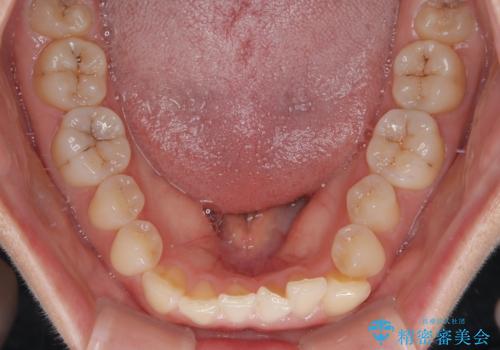

診察の結果、上下の前歯部に**叢生(そうせい/歯のガタガタ・重なり)**が認められました。

特に上の前歯にはねじれや重なりがあり、審美的にも清掃性にも影響している状態でした。